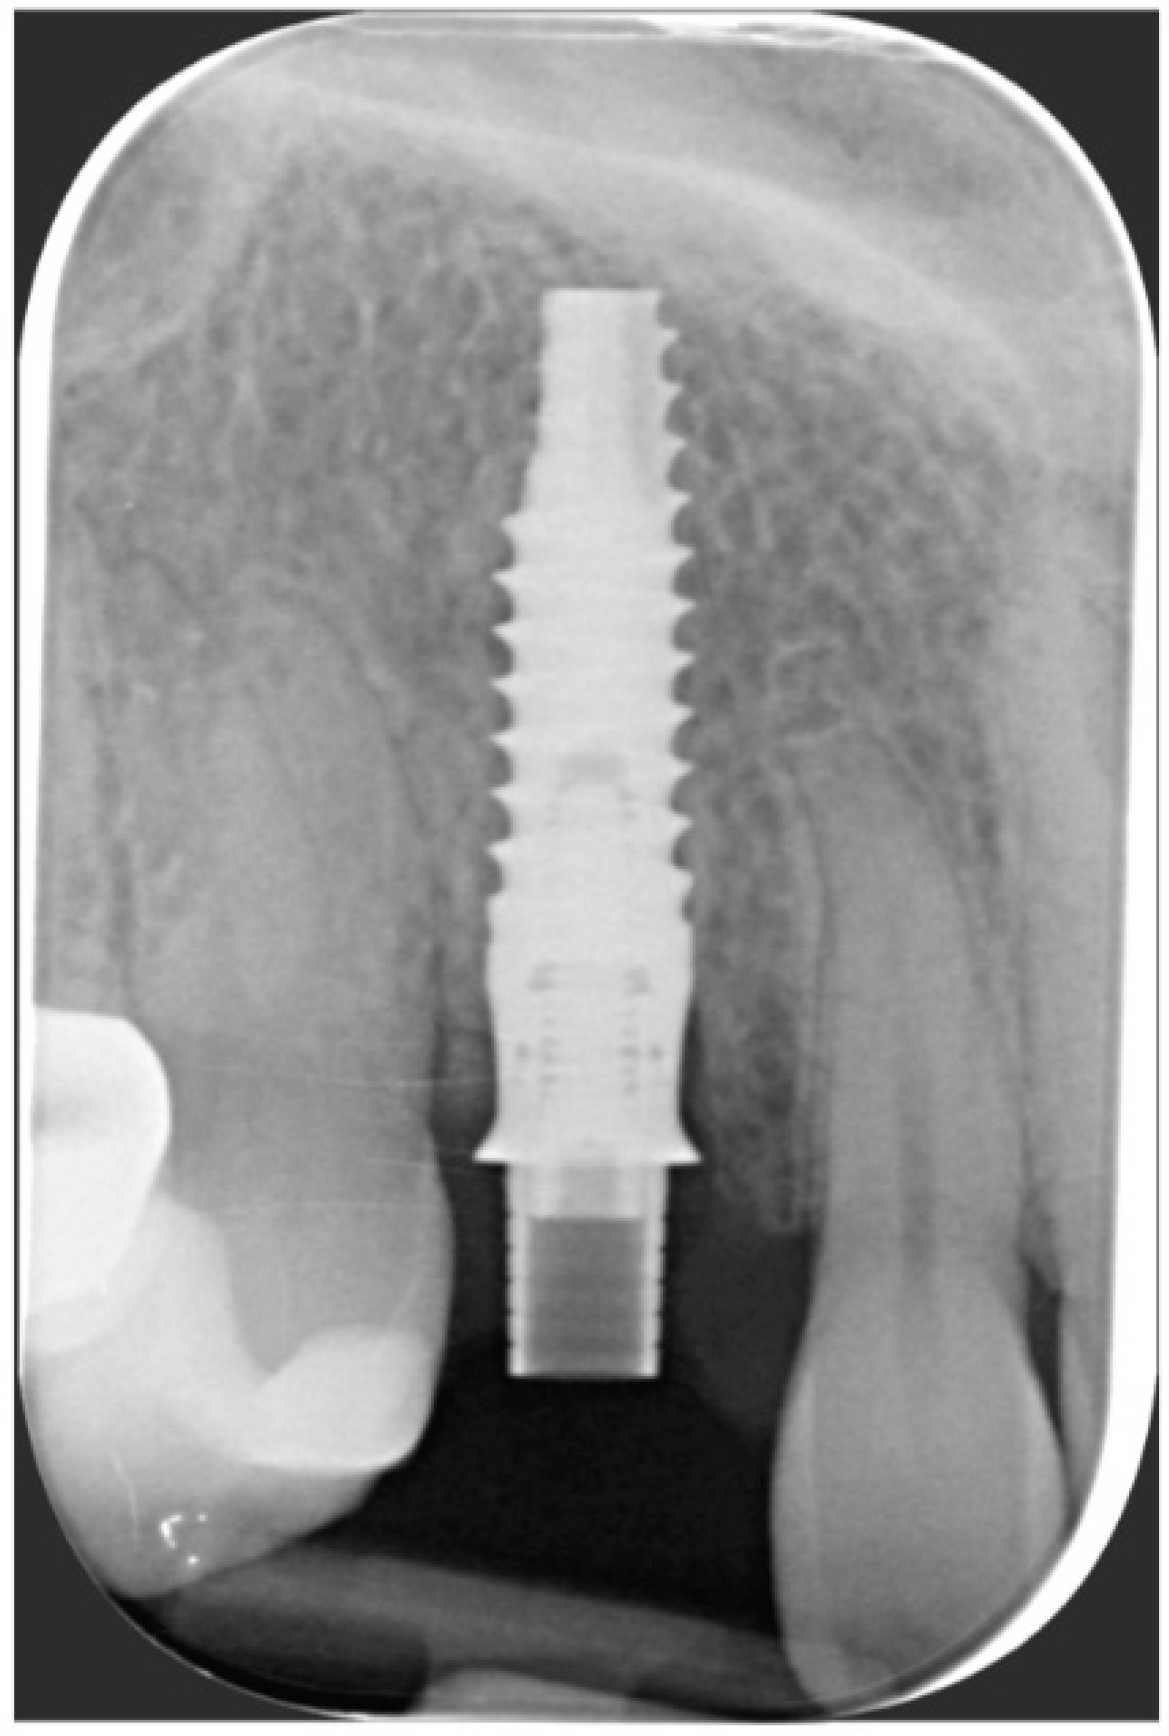

One year after final restoration placement, the clinical outcome remained stable and fully satisfied the patient’s esthetic demands (Figure 15a–c). The soft tissues were morphologically and dimensionally stable without any signs of inflammation, and the marginal bone loss evaluated with periodical X-ray scans was minimal (Figure 16).

Figure 16. Marginal bone loss evaluated with periodical X-ray scans was minimal.